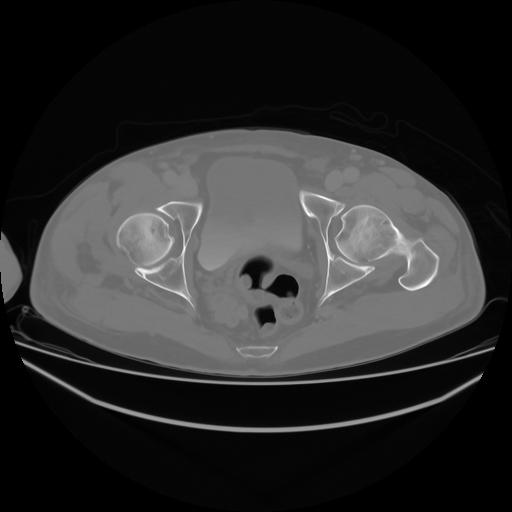

4 CUERPO,CE,Axial,3.0,CUERPO,,